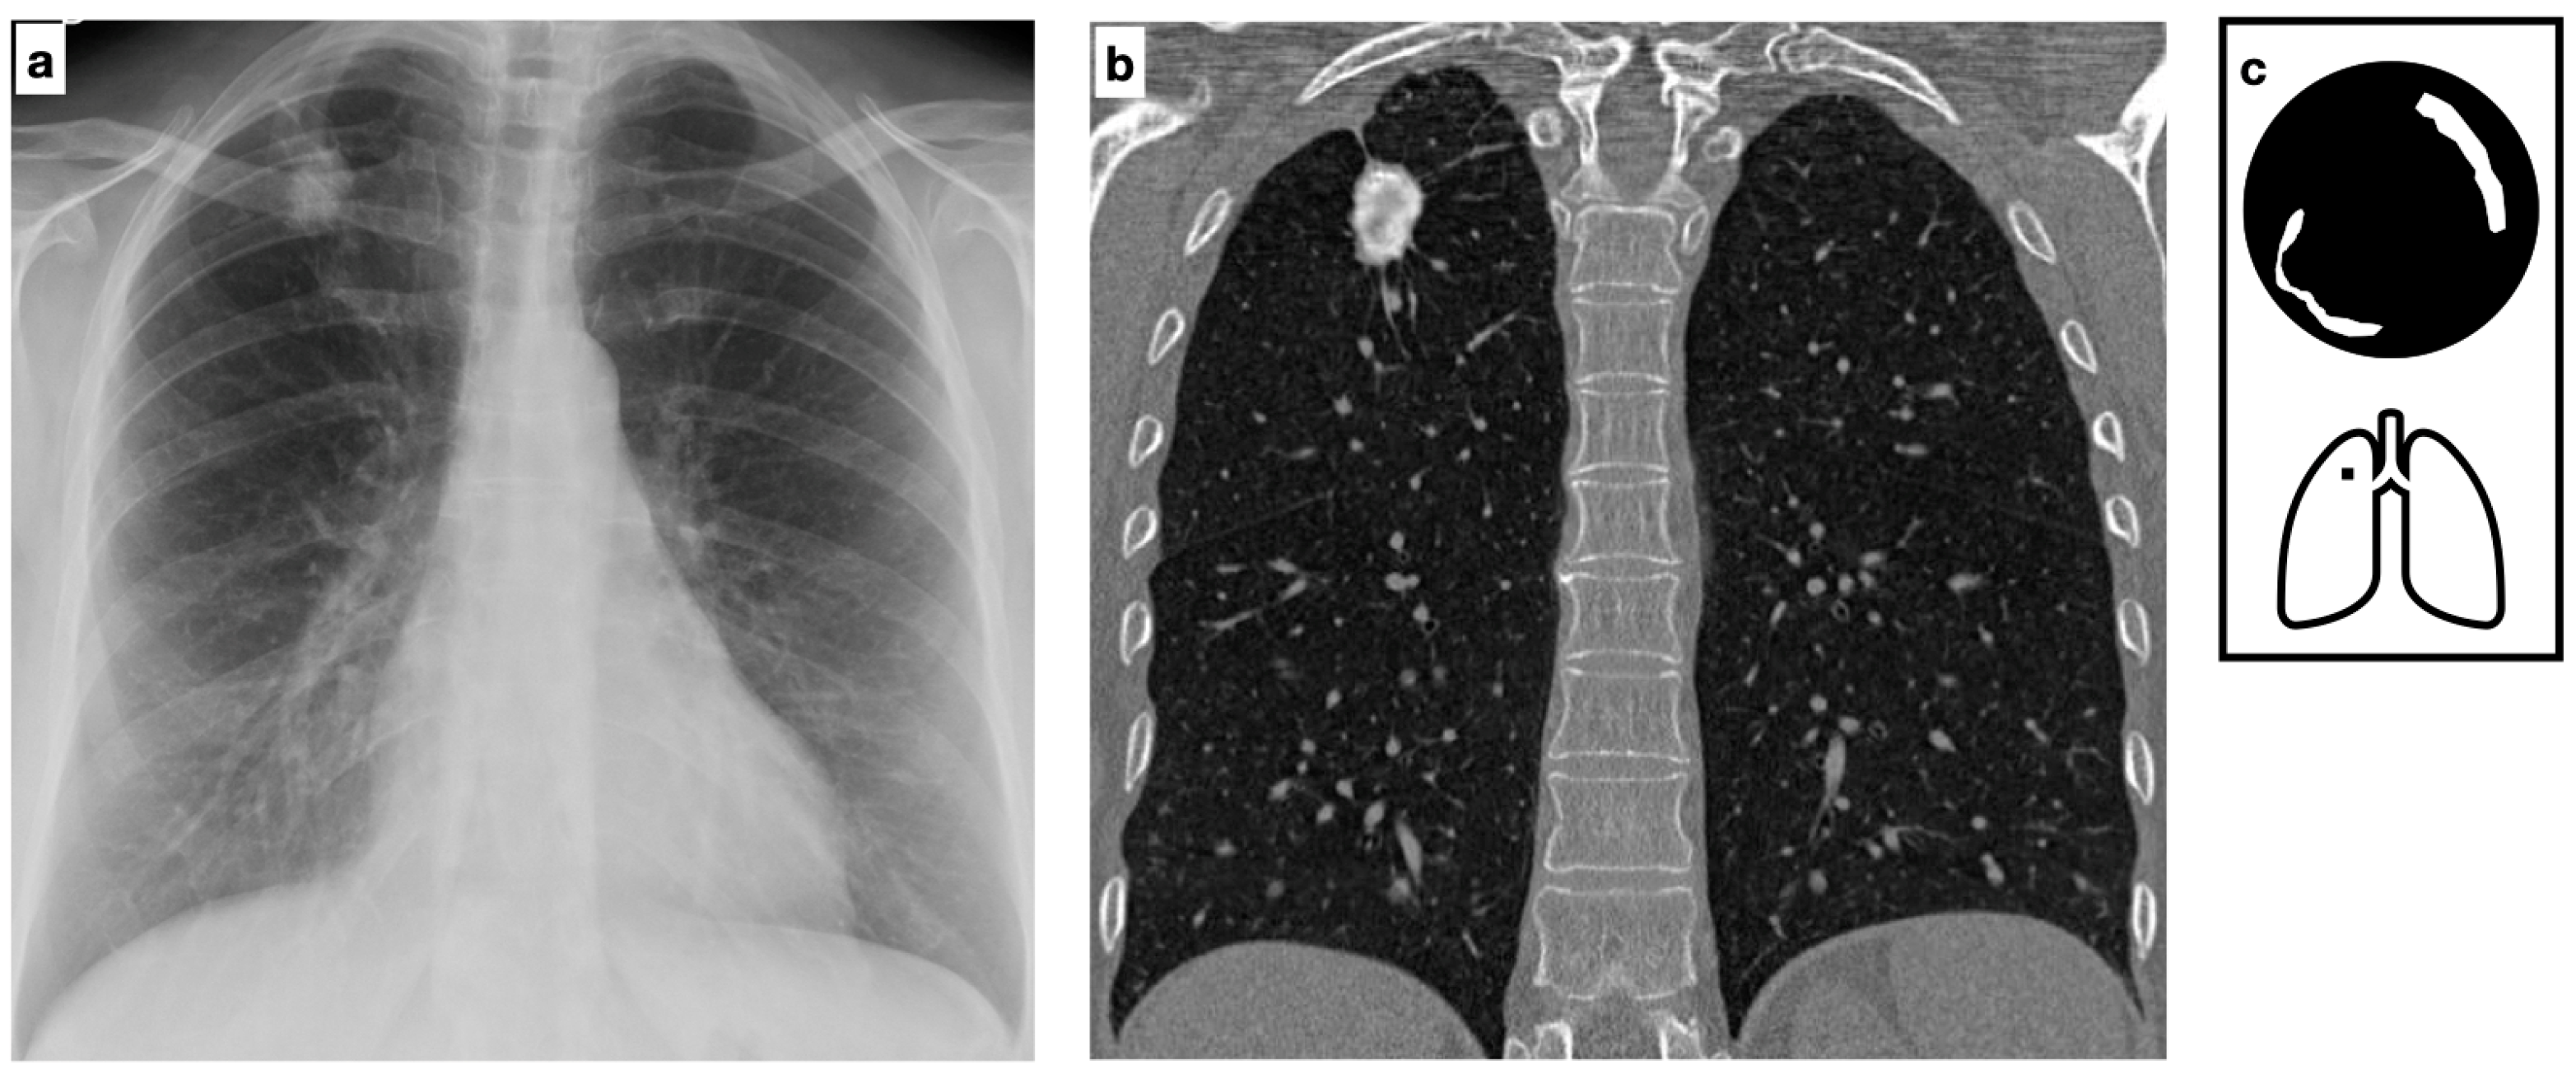

Figure 7.

Multifocal pulmonary nodules, variable in size, with smooth and lobulated contours, some of which are characterized by central calcification in a patient with biopsy-proven amyloidosis (a–c). The nodular parenchymal amyloidosis is commonly characterized by discrete nodules, heterogeneous in size, with subpleural predominance. Pattern of calcification (d).